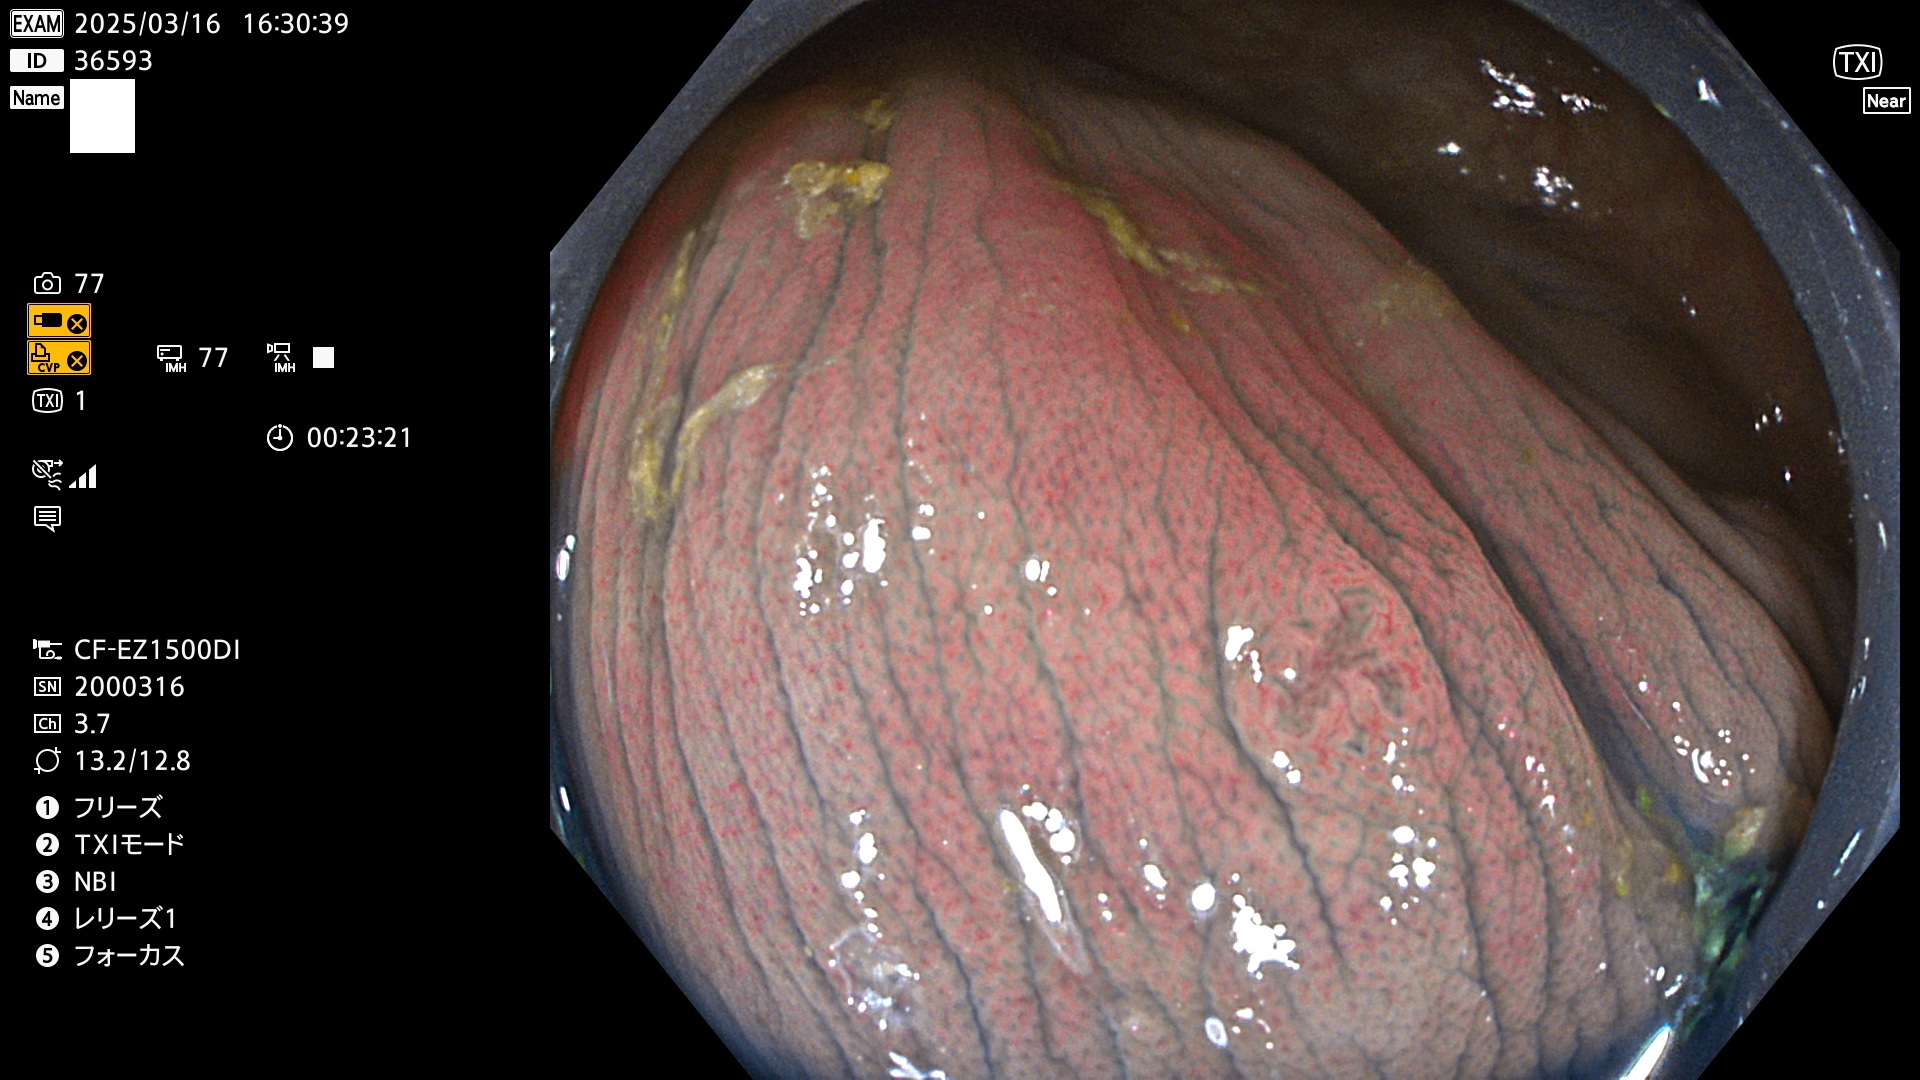

今週のUb、Uc型腺腫

完全に平坦な物をUb、陥凹している物をUcと呼びます。最も発見が難しく危険な病変です。

毎週の検査(木・金・土・日)に発見されたUb、Uc型・腺腫を、その週の日曜の夜にUPし1週間、提示します。

抽出の対象期間 2025年3月13日〜3月16日の4日間(48件の検査)12個 (12/48=25%)